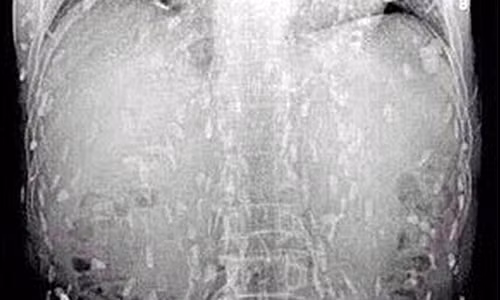

Bác sĩ cũng chia sẻ thêm, rất nhiều bệnh nhân đến khám và điều trị tại khoa Truyền nhiễm với triệu chứng nôn nhiều, đau bụng dữ dội. Khi nắn bụng bệnh nhân, thấy có khối khu trú như u; chụp X quang có hình ảnh tắc ruột nhưng không nghĩ do giun. Khi quyết định mổ, tìm vị trí gây tắc ở ruột, họ bất ngờ vì thấy búi giun to bên trong.

Hình ảnh sán dây tấn công khắp cơ thể người đàn ông.